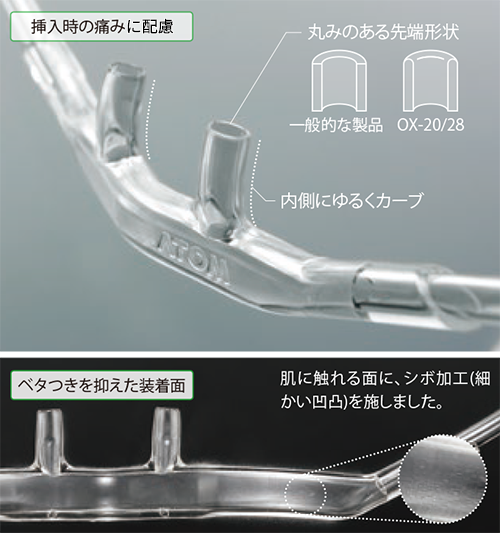

アトム酸素鼻孔カニューラ OX-20 28医用ディスポーザブル製品製品情報アトムメディカル株式会社。

アトム酸素鼻孔カニューラ。

アトム酸素鼻孔カニューラ OX-20 28医用ディスポーザブル製品製品情報アトムメディカル株式会社。